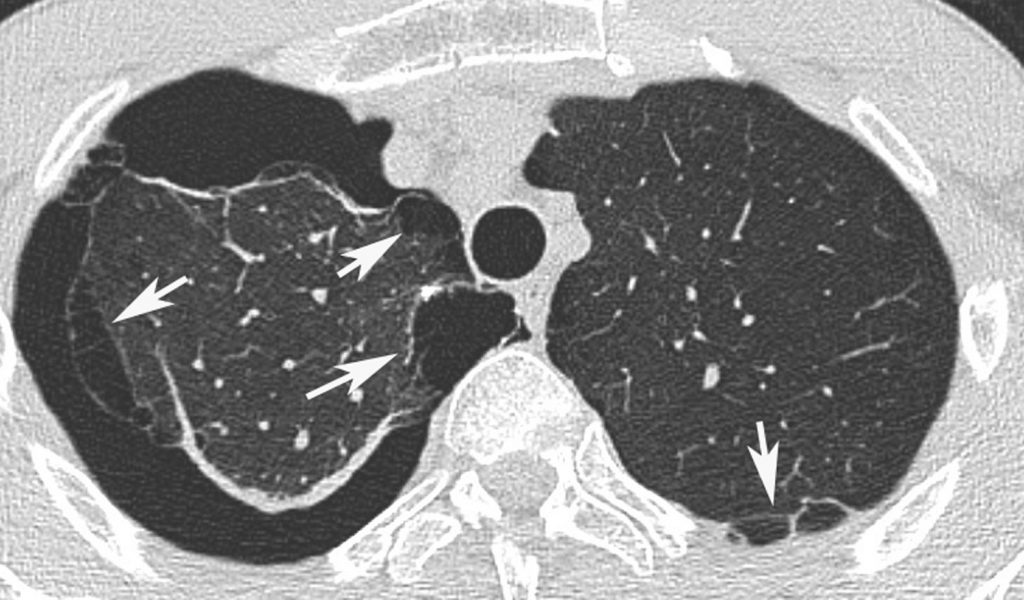

Il permet de découvrir des « blebs » apicaux ou des bulles, notamment lors du bilan préopératoire d’une récidive de pneumothorax spontané ou chez des professionnels « à risque » (plongeurs, pilotes). Il permet aussi d’identifier d’éventuelles lésions pulmonaires sous-jacentes (emphysème, maladies kystiques, surtout histiocytose langerhansienne) (figure 98.5).

Fig. 98.5. Pneumothorax en TDM avec bulles apicales.

Les images de bulles d’emphysème sous-pleural périphériques du parenchyme pulmonaire (flèches) sont facilement différenciées du pneumothorax droit qui circonscrit presque le poumon.